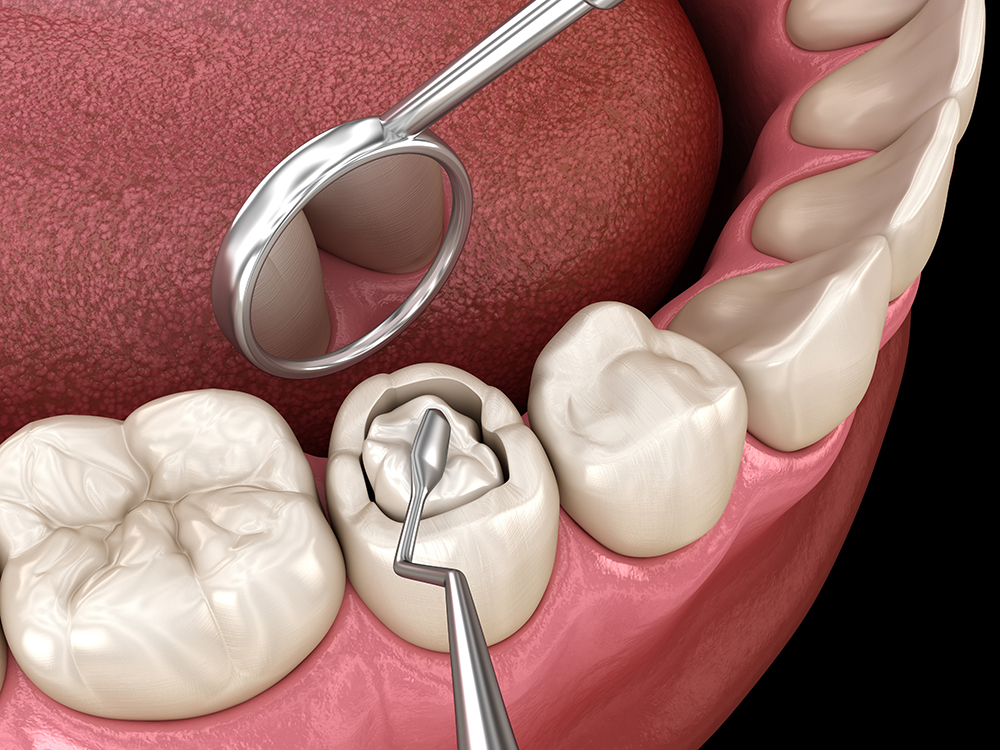

Dental restorations called composite fillings sometimes referred to as tooth-colored fillings, are made to look subtle and natural. Compared to amalgam fillings, which are darker and more noticeable to others, tooth-colored fillings look more natural and fit in well with the surrounding teeth. Composite fillings are composed of plastic and ceramic materials that adhere to teeth by a chemical process. They can be used to help fix chipped or fractured teeth, as well as to fill up decaying portions of the teeth.

4. Saves Tooth Structure – Did you know that dentists can save more of the original tooth structure when using composite fillings? This is because the composite resin material bonds to the tooth’s surface chemically, much like an adhesive does.

Dr. Khalife can accurately determine whether you need a filling during your routine check-ups. She will use a tiny mirror to examine the surface of each tooth, x-ray, and other specialized devices to closely check the area if anything seems out of the ordinary.